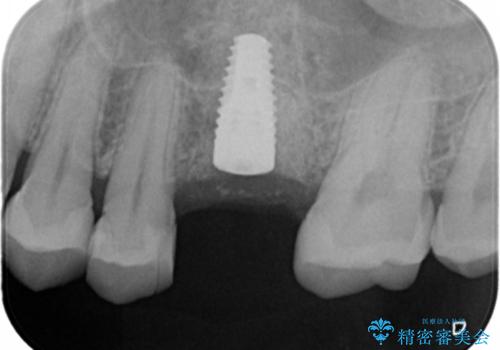

- 検査の結果、長くもたせることが困難な歯が確認された患者様です。

抜歯を行い、周囲の骨を増やしつつインプラントを埋入することとなりました。

良い位置に良い方向でインプラントを埋入することができました。